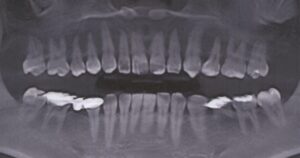

他の歯科医院にてラミネートベニアを施術されたが、ものが詰まる・見た目が良くない・噛めないとのことで治療を希望された。知り合いに当医院を勧められ来院した。

治療法

クリーニングの後、上顎前歯2本のラミネートベニア、右下臼歯部にセラミックブリッジを装着した。